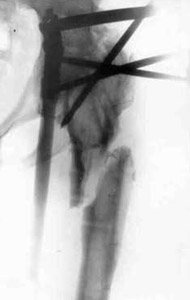

Closing of hip joint with elongation of hip.Closing of hip joint with elongation of hip.Closing of hip joint with elongation of hip.

Closing of hip joint with elongation of hip.